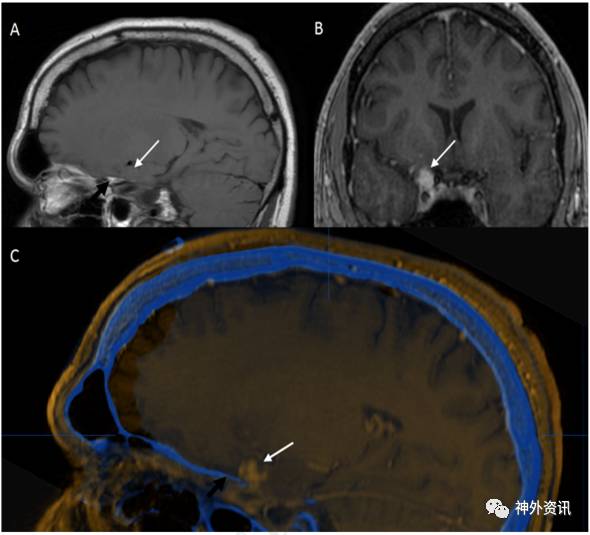

图2. A图为MRI-T1加权矢状位成像,显示一前床突上方占位病变,与硬脑膜关系密切(黑色箭头);B图为MRI-T1加权冠状位增强图像,病变位于颈内动脉上外侧;C图为MRI增强图像与CT扫描图像融合。

36岁男性患者。因外伤后行影像学检查,意外发现右侧中颅窝占位病变,无临床症状。术前MRI检查显示,右侧前床突一起源于硬脑膜的肿物,T1加权呈低信号,T2加权呈等信号,增强扫描均匀强化,考虑为脑膜瘤。经右侧翼点入路全切除病灶,无术后并发症。术后病理学检查,见病变为扩张、硬化的血管团,间质无神经组织,血管内有血栓形成,符合海绵状血管瘤。